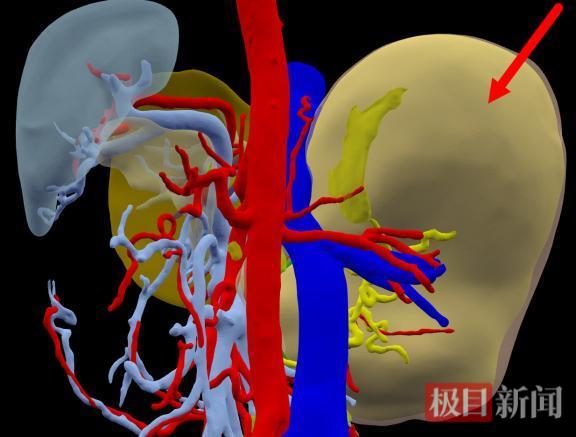

三维重建图,红色箭头示肿瘤(后面观)

通过三维重建分析,切除肿瘤及部分周边肝组织后,剩余肝的体积约占标准肝体积的50%,符合安全手术切除的条件。在充分的术前准备后,胡少勃团队为黄先生进行了手术。